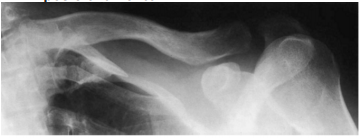

A imagem radiográfica a seguir é do posicionamento

Provas